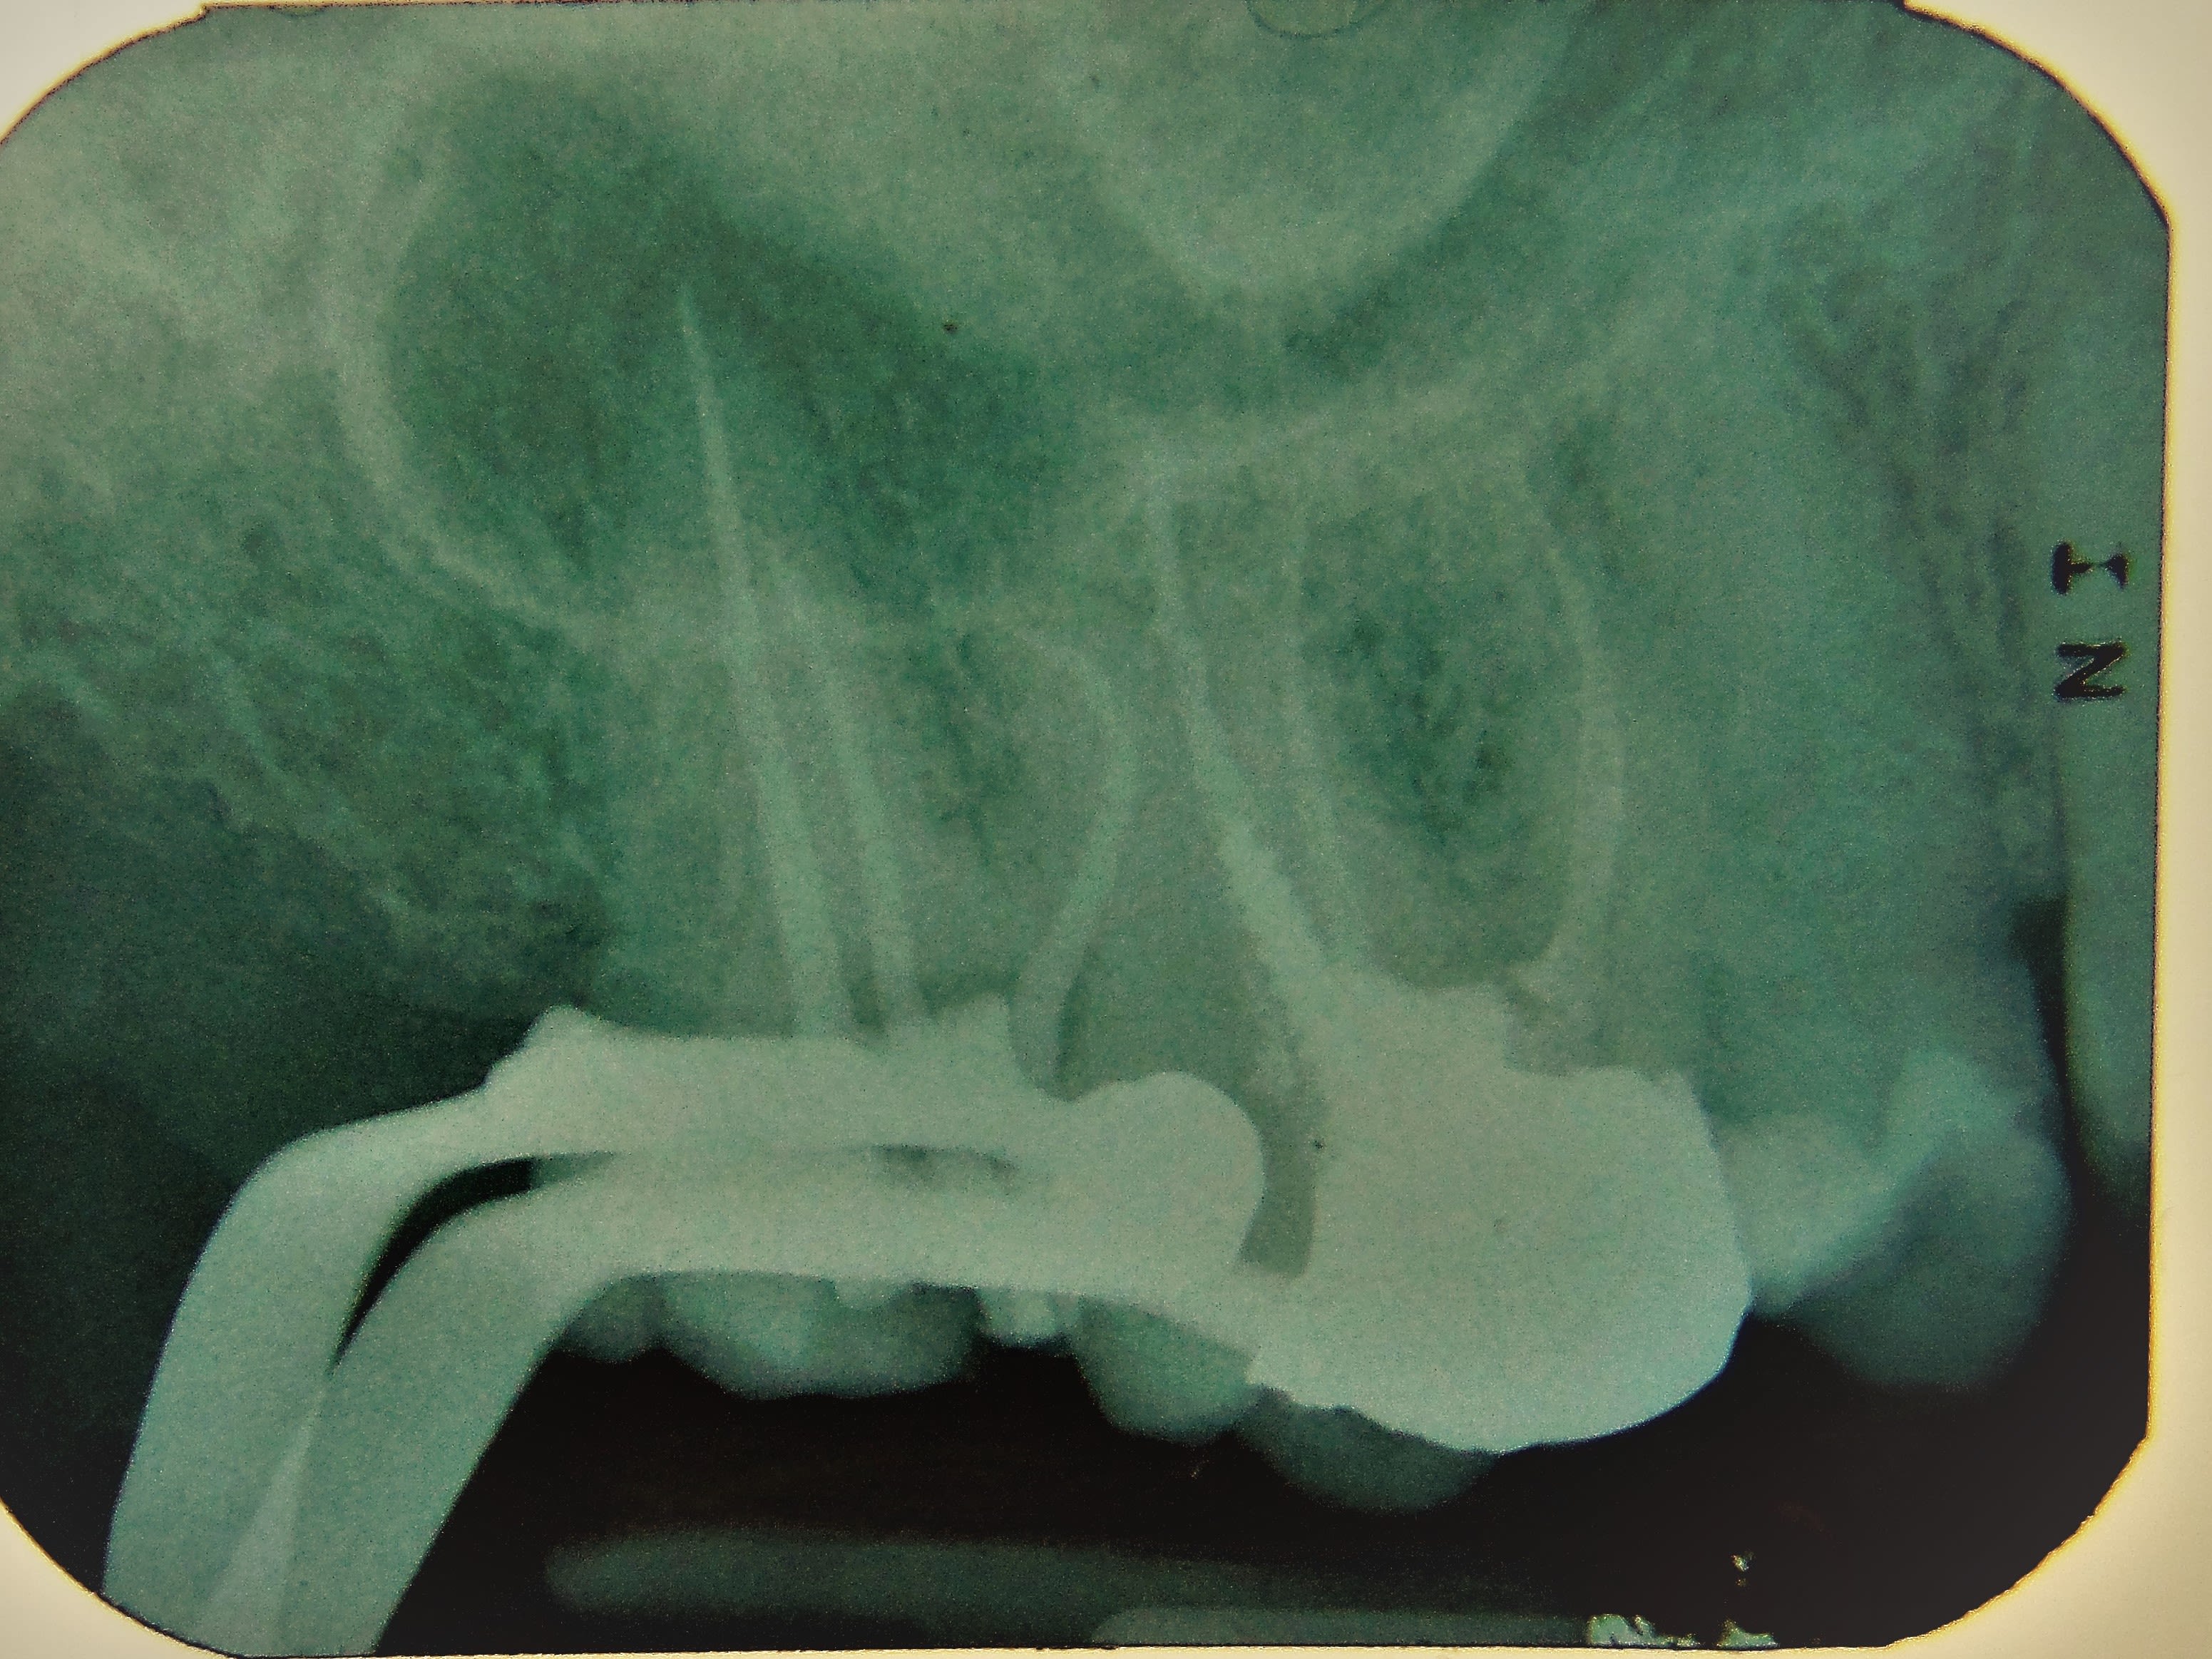

pulpite aiguë, la "tronculaire" à bien prise.

Dscf1645 3 r4cscy - Eugenol